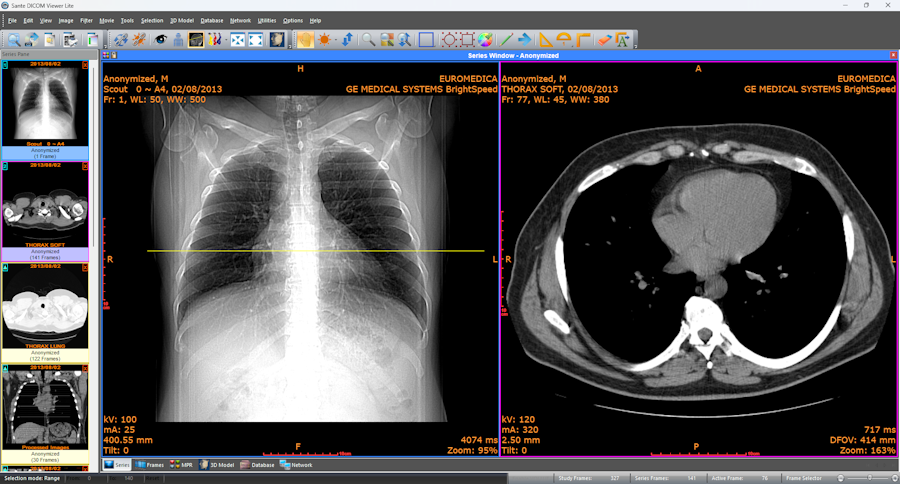

A medical imaging system involves the use of standardized data in order to be precise and consistent. The healthcare software should be able to handle various devices with complicated imaging formats. The DICOM standards permit the interoperability of imaging equipment and clinical applications.

Interpretation, processing, and display of imaging data require dependable tools for developers. DICOM library solutions give ordered access to images, metadata, and protocols of communication. Software integration is inefficient and likely to go wrong without good libraries.

Healthcare software ecosystems are vital because of seamless integration. The components of the DICOM viewer library should be able to interface well with PACS and RIS platforms. Integration with electronic health records helps to facilitate single workflow.